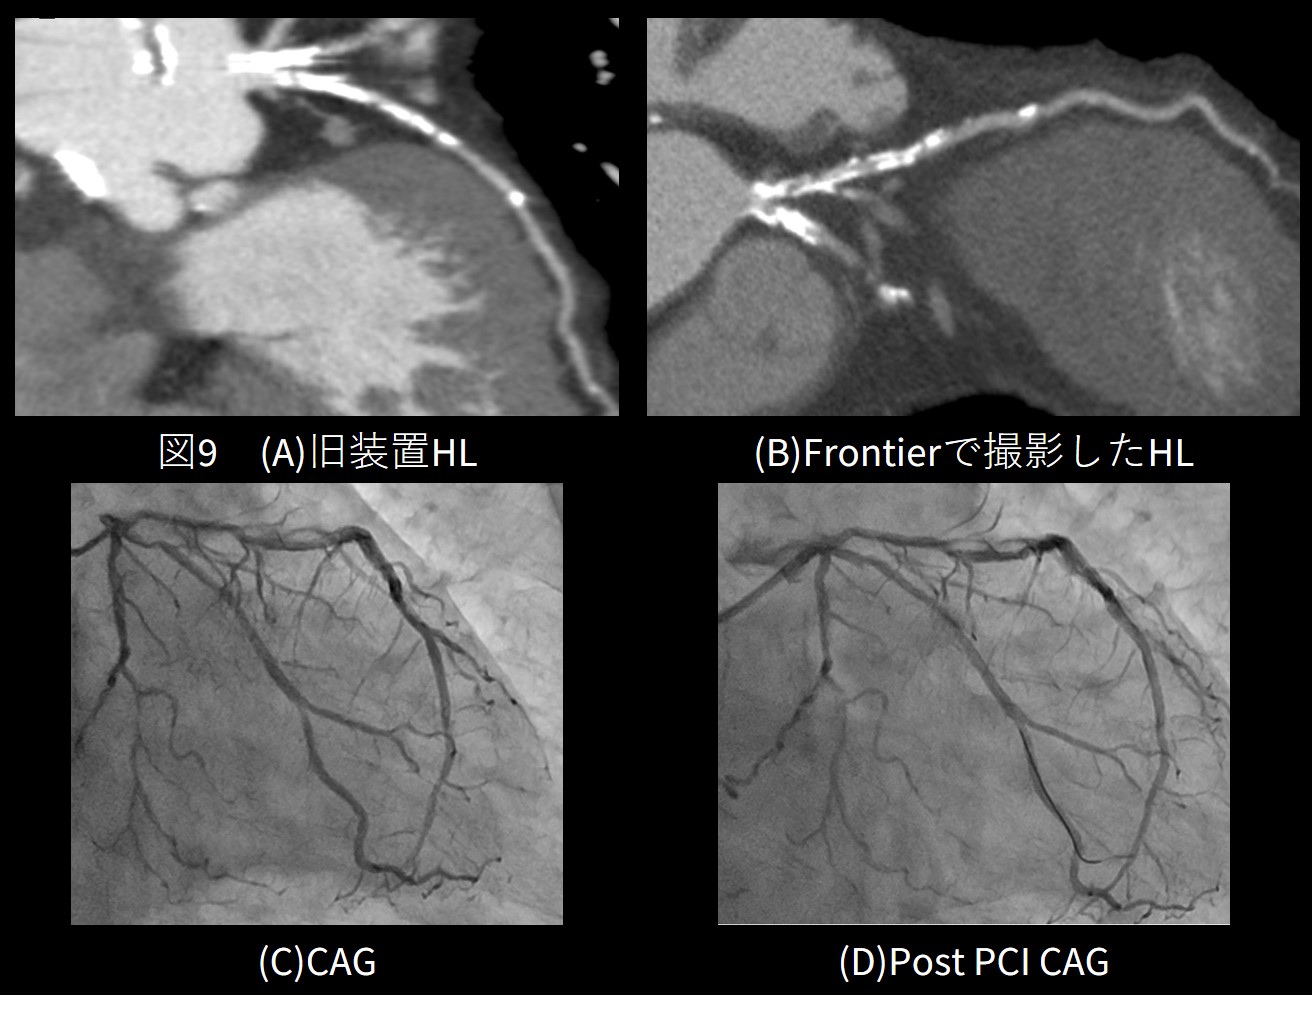

Revolution Frontierに搭載された高解像度(High Definition)モードでは、通常撮影の約2.5倍のビュー数で撮影を行い、空間分解能を向上させることができます。末梢血管などの細い血管の描出を可能にするほか、特に石灰化やSTENTをシャープな画像で観察することができます。

⑤高度石灰化症例

従来の装置では石灰化病変が存在した場合、 図9(A)のような画像になり評価困難でしたが、HDモードに使用によりブルーミングアーチファクトを軽減した高分解能画像を出すことができます。石灰化病変やSTENT病変の評価が可能となる症例も多くなりました。図9(B)はHLにプラークによる狭窄を認め、CAGとなった症例です。